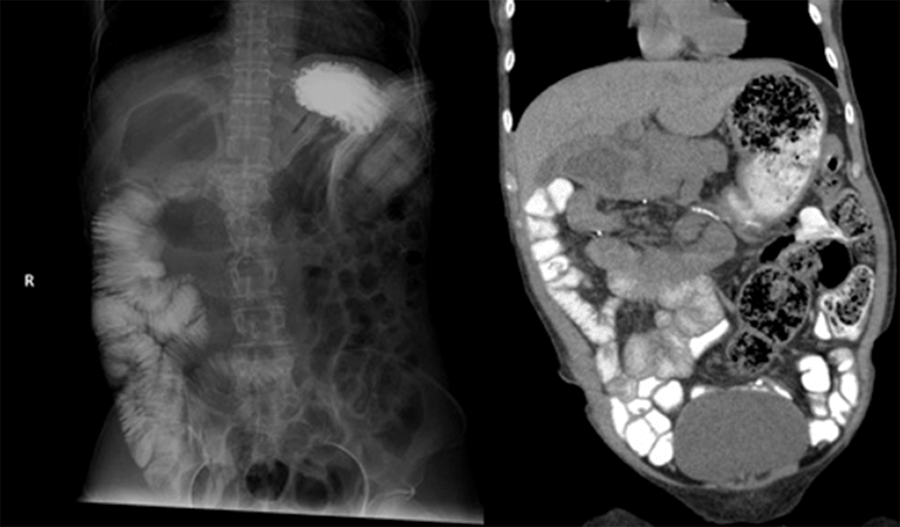

The patient’s initial radiographic workup consisted of a plain abdominal film demonstrating a large, gas-filled structure in the right upper quadrant (Figure 1). Careful analysis of a subsequent CT scan of the abdomen and pelvis with oral but no IV contrast demonstrated several findings, the first and foremost of which was what appeared to be an intussusception of the small bowel into the stomach. Upon further analysis of the CT scan, it appeared the small bowel was located predominantly on the right side of the abdomen while the colon occupied the left. While challenging to discern adequately without IV contrast, the SMV was in front of the SMA, but the two vessels were not fully transposed. An additional finding was that of contrast opacification in the right upper quadrant in the same area where a gas-filled loop of bowel had been noted on the initial plain film. Finally, the duodenum did not appear to cross the midline abdomen (Figure 2).

Figure 1. Initial Abdominal X ray Demonstrating Large Proximal Duodenal Gas Bubble. Published with Permission

Figure 2. CT Imaging. Published with Permission

Oral contrast demonstrates findings of intussusception (right); intussusceptum (jejunum) is seen within intussuscipiens (body of stomach). Oral contrast is identified within stomach and blind-ending proximal duodenum.